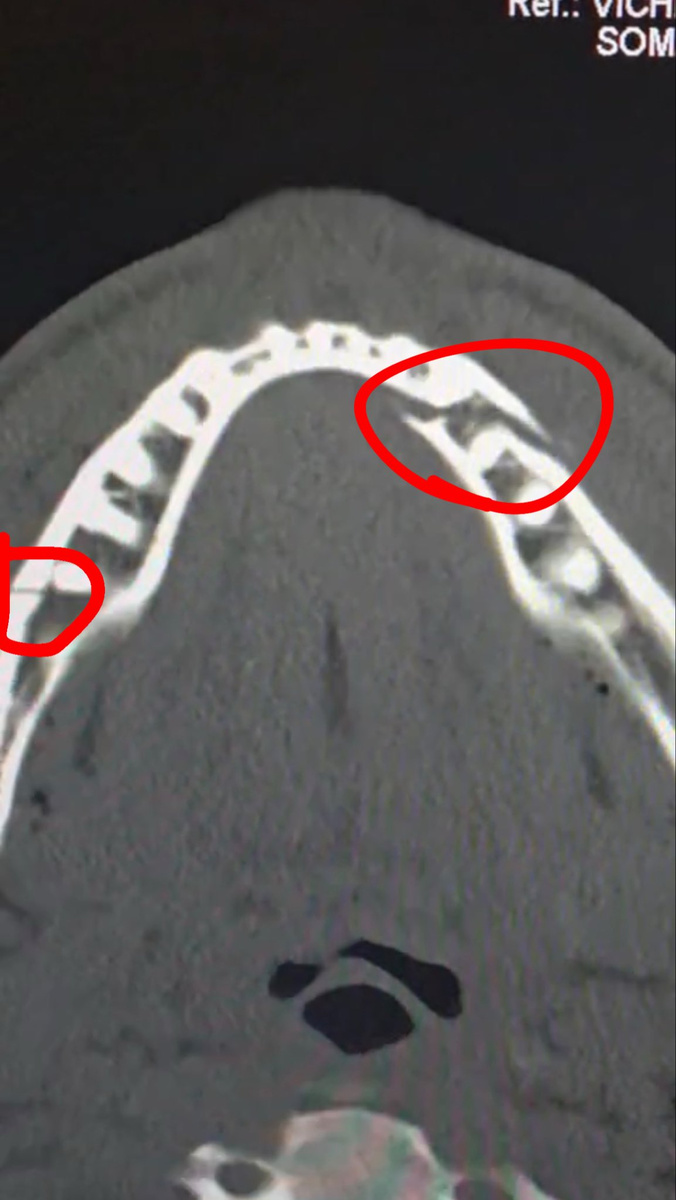

В конце концов Джошуа остановил его правой рукой, и Пол сразу же поехал в больницу с подозрением на перелом челюсти, что позже подтвердилось. Он опубликовал фото своего рентгена в соцсети с подписью: «Двойной перелом челюсти. Дай мне Канело через 10 дней

Anthony Joshua broke Jake Paul's jawView Image